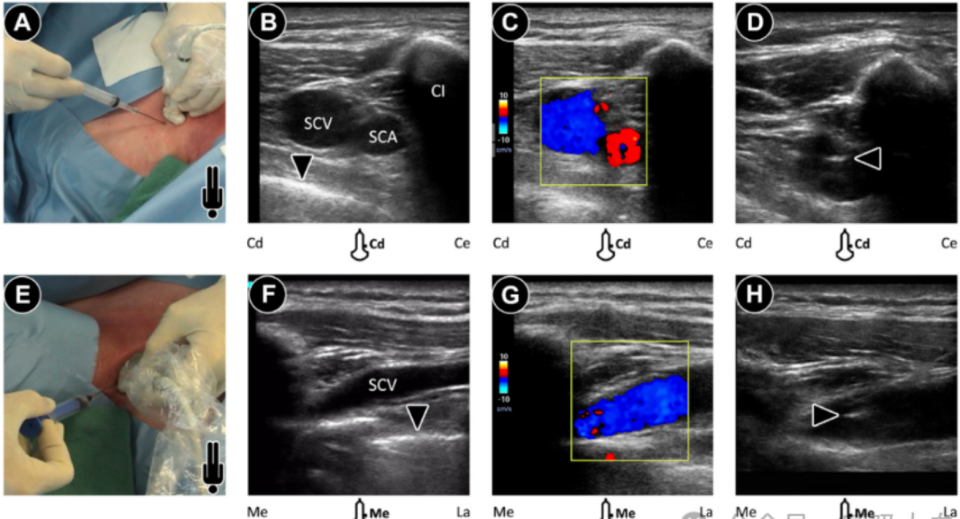

图注释:操作者可使用(A-D)短轴(SAX)平面外针头穿刺方法或(E-H)长轴(LAX)平面内针头穿刺方法来穿刺锁骨下静脉。使用(B 和 F)二维图像和(C 和 G)彩色多普勒流动图像区分静脉和动脉非常重要。(B 和 F)中的箭头表示胸膜线。(F)长轴切面显示静脉受压。(C 和 G)彩色多普勒图像显示静脉中的低速非搏动性血流,从外侧到内侧流动,方向远离探头(蓝色)。(D 和 H) 超声图像应显示针头尖端(箭头)位于静脉腔内,分别在(D)短轴切面和(H)长轴切面中。Cd,尾侧;Ce,头侧;Cl,锁骨;La,外侧;LAX,长轴;Me,内侧;SAX,短轴;SCA,锁骨下动脉;SCV,锁骨下静脉。